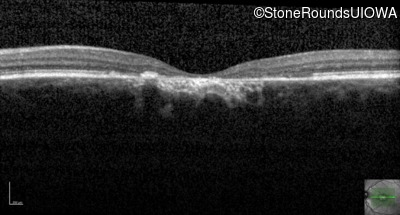

AR Stargardt Disease (IIA)

Age at visit:

47 years

OD

OS

20/125 -1

20/125 -2

Diagnosis & molecular findings

Disease

Gene

Allele 1 variant(s)

Allele 2 variant(s)

Inheritance mode

AR Stargardt Disease

ABCA4

Gly1961Glu GGA>GAA

Cys2150Tyr TGT>TAT

AR